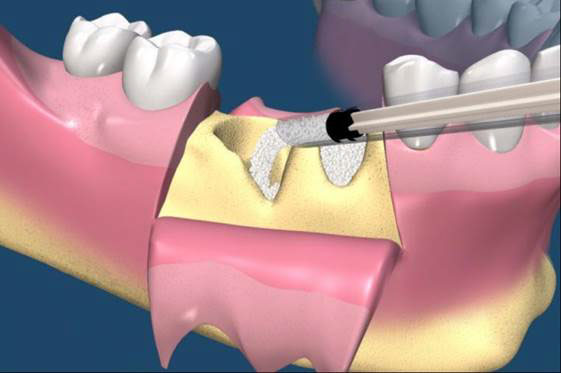

補骨手術

植牙的患者,由於有不同的骨缺損,因此大都需要補骨牙周固定,常見術式有幾下幾種:

拔牙後的齒槽吸收往往造成植牙和膺復上的困難。骨脊保存術是一項用來在牙齒拔除時最小化齒槽吸收和最大化骨形成的術式。臨床上,保存牙齒的方法很多,包括拔牙時盡量減少對周圍齒槽骨或黏膜的傷害,使用軟或硬組織移植,或合併使用再生膜和骨移植。病患於拔牙前經過仔細的評估後,採用骨脊保存術可以減少拔牙後齒槽骨的吸收,並有效的維持齒槽的外形。(圖04-08)